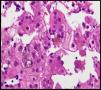

Se trata de un recién nacido a término, de peso adecuado, con estenosis de ramas pulmonares detectada por soplo cardíaco. Desde las primeras horas de vida destaca la dificultad para la alimentación, vómitos, distensión abdominal con ausencia de emisión de primer meconio. Se realiza radiografía de abdomen donde se observa ausencia de aire rectal y distensión de las asas a nivel del hemiabdomen superior, sospechándose de atresia intestinal, que se confirma. Se realiza intervención quirúrgica a las 48h de vida, practicándose resección de 23cm de intestino delgado proximales a la zona de la estenosis. Recibe nutrición parenteral durante 11 días. A partir del tercer día de vida presenta cuadro de ictericia no isoinmune con bilirrubina total máxima de 12,5mg/dl. A los 10 días de vida se observa patrón analítico de colestasis (bilirrubina total 6,41mg/dl, bilirrubina directa 4,75mg/dl, GGT 290U/l, AST 48U/l, ALT 26U/l), que se atribuye a nutrición parenteral, por lo que se suspende. Tras permanecer dicha colestasis en siguientes controles analíticos se realiza ecografía abdominal en la que se observa vesícula biliar con contenido en su interior, sin dilatación de vías biliares. Se aprecia empeoramiento progresivo de la colestasis hasta niveles máximos de bilirrubina directa de 10mg/dl, por lo que se amplía estudio etiológico. Se realiza estudio metabólico, hormonal, test del sudor, investigación de CMV y alfa-1-antitripsina, que resultan normales. En la colangio-RMN no se aprecian signos obstructivos extrahepáticos o de ramas principales hepáticas. Se realiza gammagrafía ácido iminodiacético hepatobiliar (HIDA), que muestra paso de contraste a duodeno. Se practica biopsia hepática en la que destaca paucidad de vías biliares (fig. 1) que, asociado a colestasis, cardiopatía y facies peculiar (fig. 2) sugiere el diagnóstico de SA. Se realiza estudio oftalmológico y radiografía vertebral que son normales. El patrón de colestasis sufre un empeoramiento progresivo (cifras máximas de GGT de 1.500U/l), con hiperbilirrubinemia conjugada alrededor de 12mg/dl a pesar del tratamiento con ácido ursodeoxicólico e hipercolesterolemia severa (máx 450mg/dl), apareciendo prurito de difícil control, junto con esplenomegalia progresiva secundaria a hipertensión portal, precisando trasplante hepático de donante vivo emparentado (madre) a los 2 años de edad sin incidencias y buena evolución posterior. El análisis del gen JAG1, detecta una transversión de C por A (c.756>A) en heterocigosis que presumiblemente, a nivel de la proteína, determina un codón de parada prematuro (p.Tyr255*), descrita previamente en la bibliografía como mutación asociada al síndrome de Alagille7,8.

El padre (27 años) presenta facies peculiar (fig. 2), y antecedente de estenosis de rama pulmonar izquierda que precisó intervención quirúrgica en edad pediátrica sin repercusión hemodinámica en la actualidad, y colestasis anictérica (AST/ALT 130/165U/l, GGT 968U/l, FA 442U/l, Bil 0,83mg/dl, Col 210mg/dl) detectada a los 21 años como hallazgo casual en analítica rutinaria atribuida a enolismo. A raíz del diagnóstico del hijo, se realiza colangio-RMN, objetivando una vía biliar extrahepática de escaso calibre con ausencia de visualización de la vía biliar intrahepática y una biopsia hepática que muestra ausencia de ductos biliares en más del 50% de los espacios porta, hipoplasia vía biliar y hemosiderosis intrahepatocitaria. A raíz del diagnóstico de SA en el hijo, se ha diagnosticado también al padre, quién presenta una expresividad menos severa. Cabe destacar la variabilidad de la expresión clínica intrafamiliar, con una afectación hepática importante en el hijo y, en cambio, muy leve en el padre a la edad de 27 años (figs. 1 y 2).